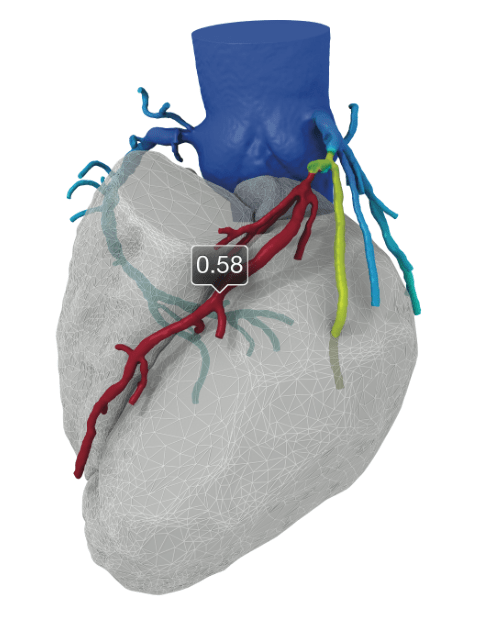

Heart and vascular specialists at UH Harrington Heart & Vascular Institute are also continuing their groundbreaking work using fractional flow reserve computed tomography (FFR-CT) technology in the diagnosis of coronary artery disease. UH Cleveland Medical Center was the first site in the U.S. to use the technology after its November 2014 approval by the U.S. Food and Drug Administration. This imaging is currently available at UH Cleveland Medical Center, UH Ahuja Medical Center and UH Elyria Medical Center.The technology, developed by HeartFlow, Inc. is the first and only noninvasive diagnostic test specifically designed to provide cardiologists with both anatomic and functional information regarding the extent and significance of coronary artery blockages. It takes coronary CTA scans and combines them with proprietary computer algorithms based on computational fluid dynamics to create a color-coded, 3-D model of the patient's three major coronary arteries, showing both derived FFR information and anatomy. FFR-CT is calculated as a distal-to-proximal pressure ratio, just as it is derived from invasive measurements in the catheterization lab.